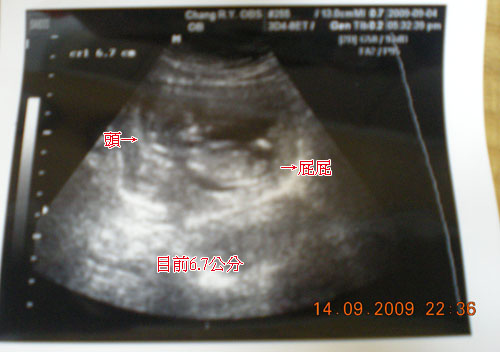

第十二週,寶寶已經6.7公分了~好期待知道是男生還是女生喔^^

最近也比較不會吐了~一定是寶寶很乖的關係^^